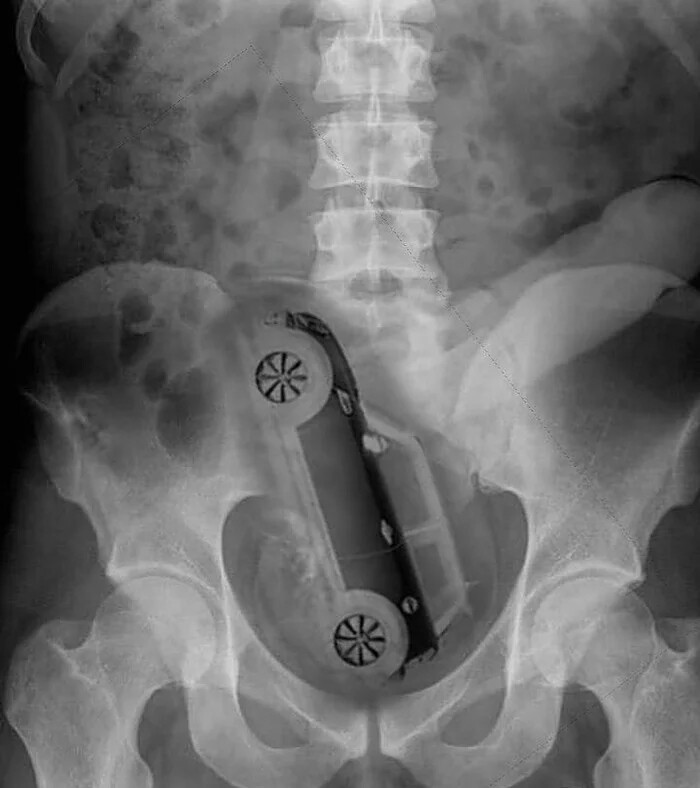

9. Модель машины "Мини Купер"